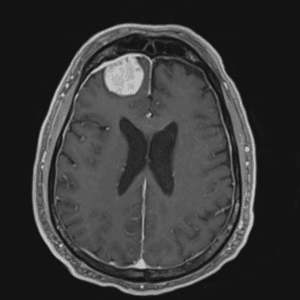

Case #42

Giant cerebral aneurysm